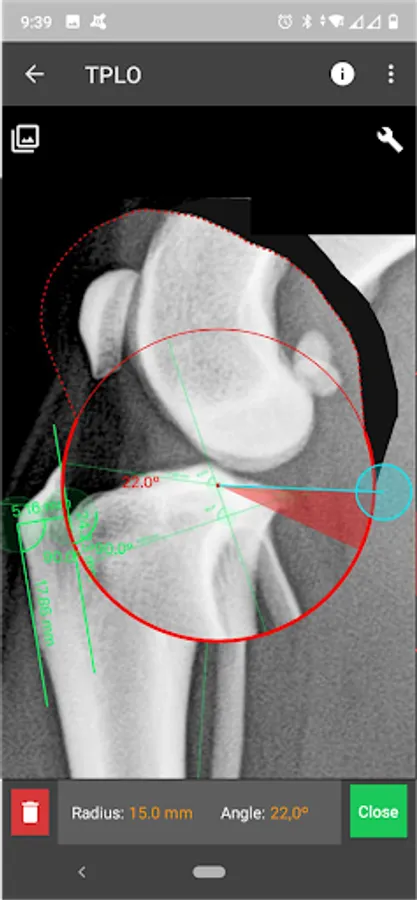

b) Radial measure/Circle draw.

f) Circular cut, TPLO.